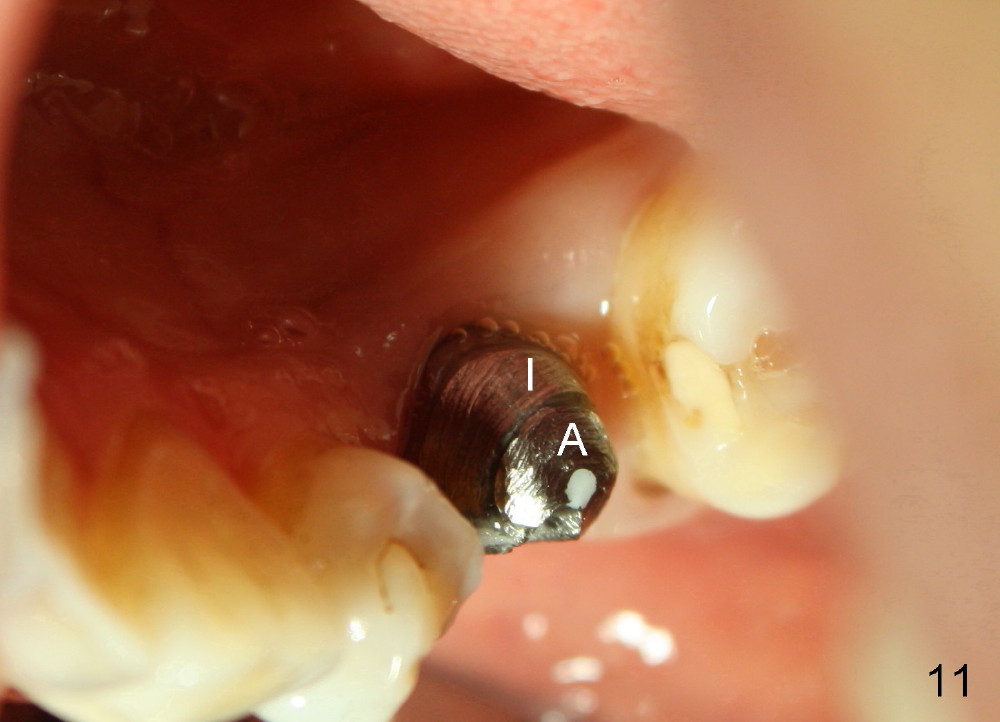

Six months postop, bone density around the implant increases (Fig.9).  There is slight gingival recession buccal to the implant (Fig.10 arrow).  A short abutment is placed and prepared short (Fig.11 A); the margin is prepared as low as possible in the implant (I).